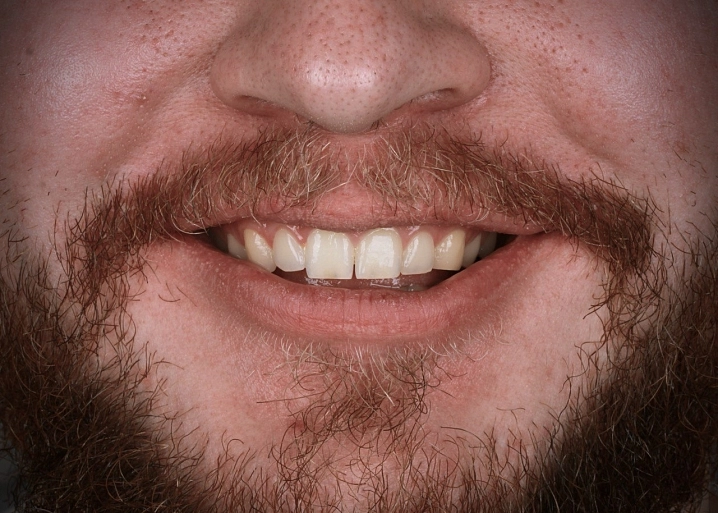

Прочный протез стал настоящей находкой для людей с аллергией на металлы, в частности, на сплав кобальта и хрома, используемый в металлокерамике.

Существует 2 вида реставраций: с нанесением керамической массой и методом раскрашивания. Второй вариант в нашей клинике применяется чаще всего. Этот метод дает высокий эстетический результат. Первый вариант с нанесением керамики имеет недостаток, керамика может со временем скалываться, что вызывает неудобство в использовании протеза.